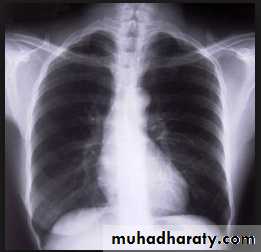

Chest X-ray:

Used In:

A -Preoperatively. B- Pre-employment .

C - Patient complains from respiratory symptoms.

D - Patient complains from cardiovascular symptoms.

Routine Examination includes

P-A view , Other supplementary views are done according to the case. So all Patients admitted to hospital should have P-A X-ray In standing erect view in complete inspiration